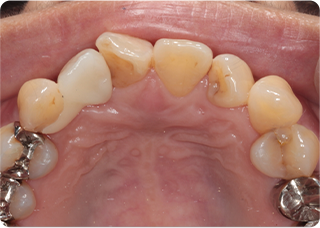

セラミッククラウン症例②

術前

仮歯

術後

| 主訴 | 前歯を綺麗にしたい、隙間が気になる |

|---|---|

| 治療期間/回数 | 4ヵ月、6回 |

| 価格(税込) | 792,000円(税込) |

| リスク・副作用 | セラミック破損の可能性 |

| ポイント | 仮歯で歯ぐきの状態を整え、自然な色、形となるようにオーダーメイドでセラミックを盛り、クラウンを作製した。 |